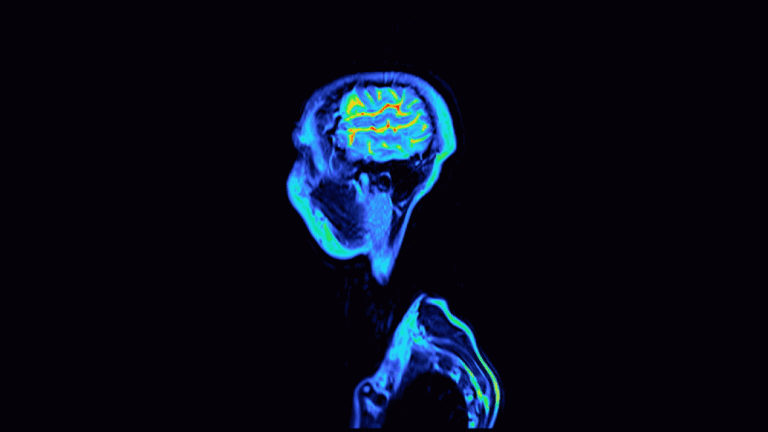

A new study analysed networks in the brains of people of different ages and found that brain aging appears to accelerate at certain points in life. (Image credit: Eugene Mymrin/Getty Images) The study found that the human brain suddenly begins…